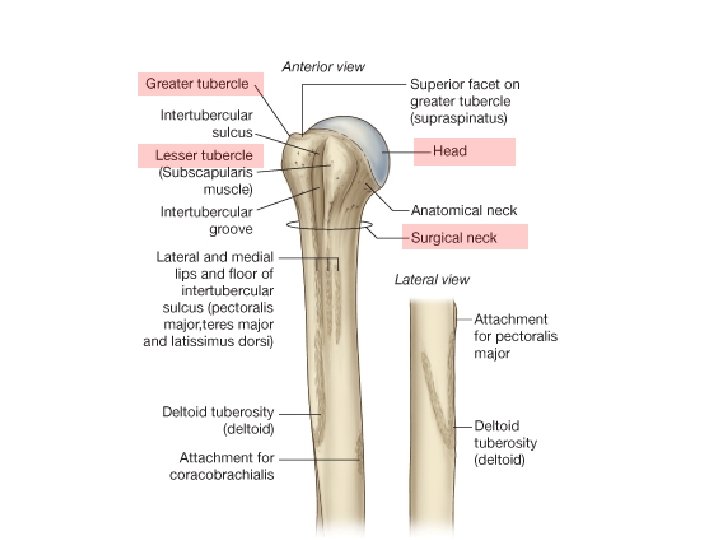

Shoulder Osteology Xray Muscles CTMRI Shoulder Osteology Xray

Shoulder • • Osteology X-ray Muscles CT/MRI